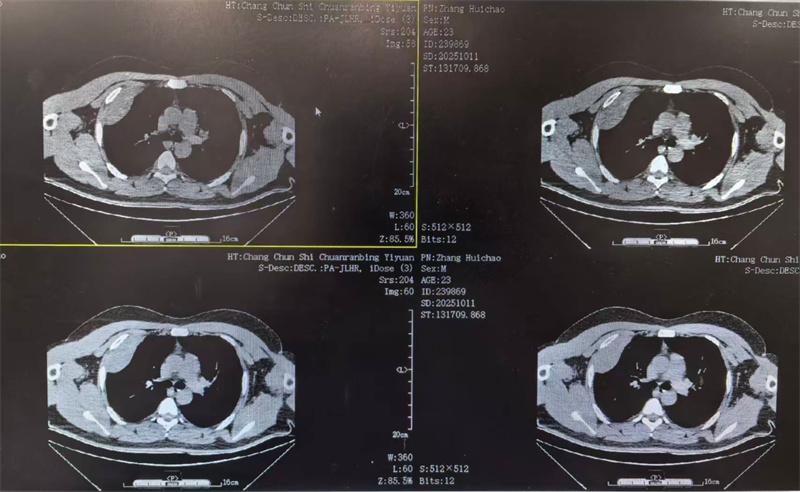

四个月前,23岁的小雨(化名)因胸闷前往医院就诊,CT检查结果显示右侧胸腔靠上位置出现包裹性脓胸,并进行穿刺检查,最终确诊为结核性包裹性脓胸,这个消息让小雨和家人陷入了深深的焦虑之中。

看着日益憔悴的小雨,医生建议手术治疗。术前,田子刚主任和宋巍峰医生在全面评估了小雨各项指标后,确定符合手术标准,便与麻醉科以及护理团队紧密配合,为小雨实施胸腔镜下胸膜剥脱术。

手术室内,胸腔镜在田子刚主任和宋巍峰医生紧密配合操控下,通过小小的切口精准插入小雨体内。在高清显示屏上,胸腔内的情况清晰可见。

经过3个小时的紧张操作,包裹的脓肿被完整剥除,病灶彻底清除。术后切开脓肿,其内可见脓液,干酪物和坏死肉芽组织。

小雨的手术切口很小,大约只有4厘米,出血量也仅100ml,这对小雨的愈后起到了很好的作用。术后,小雨在医护人员的精心照料下恢复得很快,于10月24日顺利出院。